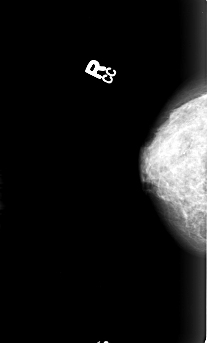

FILE: B_3005_1.LEFT_CC.OVERLAY

TOTAL_ABNORMALITIES 1

ABNORMALITY 1

LESION_TYPE CALCIFICATION TYPE PUNCTATE-AMORPHOUS-PLEOMORPHIC DISTRIBUTION CLUSTERED

ASSESSMENT 4

SUBTLETY 3

PATHOLOGY MALIGNANT

TOTAL_OUTLINES 1

BOUNDARY